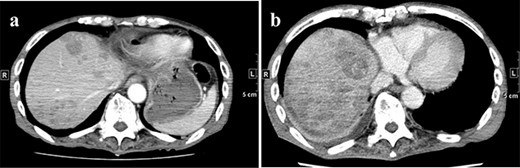

A 77-year-old man was referred to the Department of Gastroenterology at our hospital for suspicion of hepatocellular carcinoma and cancerous peritonitis. He was scheduled to be hospitalized for a thorough examination at a later date. However, 3 days after his first visit, he returned to the Emergency Department with a complaint of abdominal distension. He was hospitalized on the same day with a diagnosis of intra-abdominal bleeding due to a ruptured tumor in the lateral section of the liver. Computed tomography (CT) and magnetic resonance imaging (MRI) revealed a tumor with a maximum diameter of 8 cm in the lateral hepatic region and ascites around the liver and in the pelvic floor. Dynamic CT showed blood vessel-like early staining inside the tumor, and the contrast effect gradually enhanced (Fig. 1). During gadolinium ethoxybenzyl diethylenetriamine pentaacetic acid-enhanced MRI, this contrast effect gradually increased from the peripheral part toward the hepatocyte phase from the arterial phase (Fig. 2). Levels of tumor markers (alpha-fetoprotein, protein induced by vitamin K absence or antagonist-II, carcinoembryonic antigen and carbohydrate antigen 19–9) were within the normal range (Table 1). Based on the imaging findings, a diagnosis of spontaneously ruptured hepatic hemangioma was made. Since the patient’s general condition was stable and there were no findings suggestive of active bleeding, he decided to undergo elective surgery. Thus, he was not requested to continue being hospitalized and was discharged. Six days after discharge, he was transported to the emergency room in a state of shock and was hospitalized the same day. With the diagnosis of hemorrhagic shock due to re-rupture of the liver tumor (Fig. 3), emergency transarterial embolization (TAE) was performed. No apparent extravasation was observed on angiography, and A3 was embolized. Seven days later, he underwent left lateral hepatic segmentectomy. The postoperative course was generally good. The post-ruptured tumor was found in the left lateral segment, the cut surface was white, the edges were brown and the boundaries were unclear (Fig. 4). Histopathological examination revealed that sections of the white and brown parts of the margin were viable tumors, showing highly atypical spindle-shaped cells, arranged like sinusoidal vessels and partly solid, and there were many mitotic figures. There was no capsule, and the tumor infiltrated the surrounding liver parenchyma (Fig. 5a–c). Immunostaining showed CD31 (+), CD34 (partially positive), CK-CAM5.2 (−), α-SMA (−), HMB45 (indeterminate) and p53 (+), and the patient was diagnosed with hepatic angiosarcoma (Fig. 5d). Fever was observed 21 days after surgery, and CT was performed, revealing multiple masses in the liver (Fig. 6a). Another CT scan was performed 27 days postoperatively, which suggested that the liver masses were rapidly increasing; hepatic angiosarcoma recurrence was then confirmed (Fig. 6b). The patient requested the best supportive care at home and was discharged 31 days after the operation. He died at home 36 days after surgery.

(a) CT on Day 21 after surgery. Multiple tumors are found in the liver. (b) CT re-examination performed 27 days after the operation shows multiple rapidly increasing liver masses. CT, computed tomography.